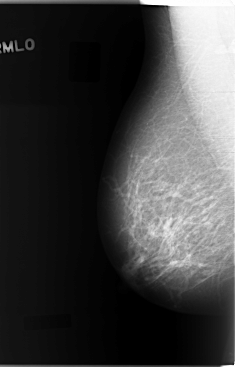

C_0088_1.RIGHT_MLO

RIGHT_MLO LINES 5872 PIXELS_PER_LINE 3752 BITS_PER_PIXEL 12 RESOLUTION 50 NON_OVERLAY